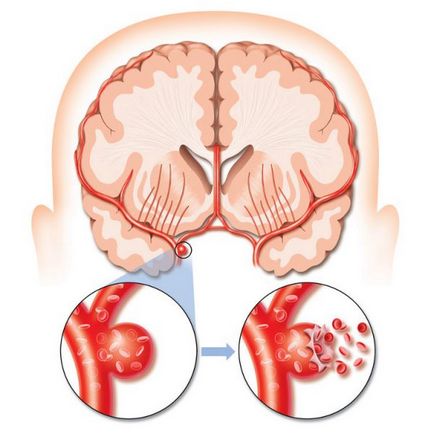

Idővel, intenzív a vér áramlását a lényege a fejlődési rendellenesség vezet bővítése az érintkeztetés az artériák és vénák (dilatáció). Ez gyengíti az erek, így hajlamos a törés és vérzés. A szállítási artériák hajlamosak a aneurizmák, amely végül vezethet törés és vérzés az agyban.

agyvérzés

A vérzés kockázata körülbelül 2-4% évente. A következő évben az első vérzés kiújulás kockázata emelkedett a legnagyobb. Miután az első vérzés a kezelés hiányában veszélyét növeli újra vérzés három példányban. De aztán, ismeretlen okból, a kockázat a visszatérő vérzés fokozatosan csökken évről évre.

Vérzés gyengülése miatt az erek miatt a tolatási folyosón artériás közvetlenül a vénába a AVM. Rövid távú és hosszú távú neurológiai hatásait vérzés függ a mennyiség a kiömlött vér és vérzés lokalizáció. Néhány tényező felelős spontán vérzés a gyógyszeres kezelés hiányában, vagy annak használatát tartalmazzák: